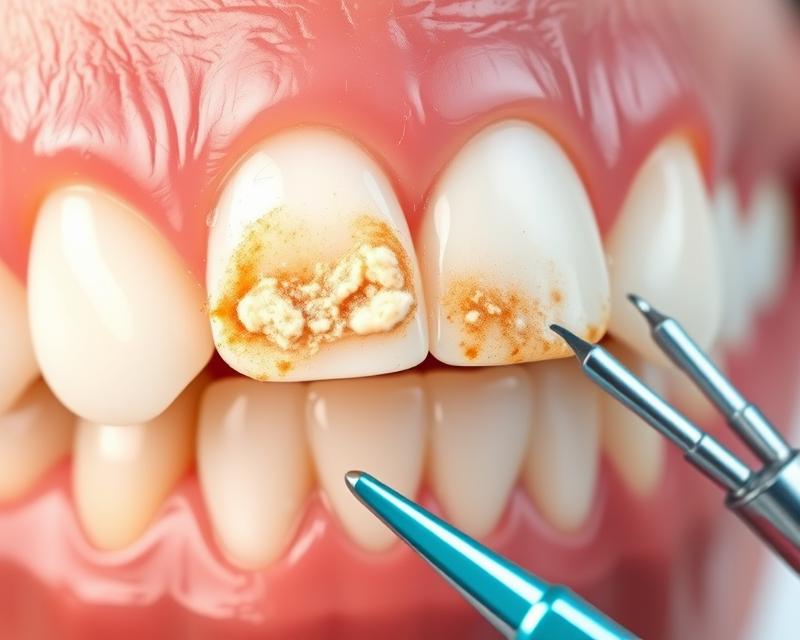

Kamień nazębny to twarda substancja, która osadza się na zębach. Powstaje poprzez mineralizację płytki nazębnej, proces ten rozpoczyna się zaledwie kilka godzin po umyciu zębów. Miękki nalot, złożony z bakterii oraz resztek jedzenia, pod wpływem śliny i zawartych w niej soli mineralnych, zaczyna twardnieć. Z upływem czasu zmienia się w ciemniejszy i jeszcze bardziej zwapniały osad, co sprawia, że jego usunięcie staje się coraz trudniejsze.

Jego obecność może prowadzić do poważnych problemów zdrowotnych, takich jak:

- próchnica,

- choroby dziąseł,

- przebarwienia zębów.

Objawy kamienia nazębnego są z reguły dość łatwe do zauważenia. Na przykład, różowe lub żółte plamy, które pojawiają się w przestrzeniach między zębami, można dostrzec gołym okiem. Jeśli te przebarwienia nie ustępują pomimo skrupulatnego szczotkowania i nitkowania, konieczna będzie wizyta u dentysty. Kamień nazębny może prowadzić do poważnych schorzeń, takich jak: